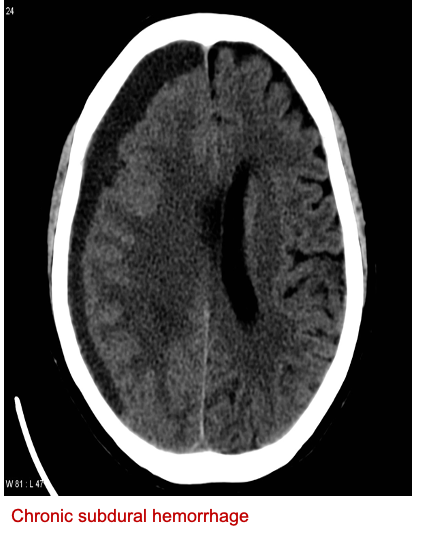

Concave esccentric in shape, ++++ hypo dense

MMA vessel left /-/ contralateral shift - hypodense acute infacrtion